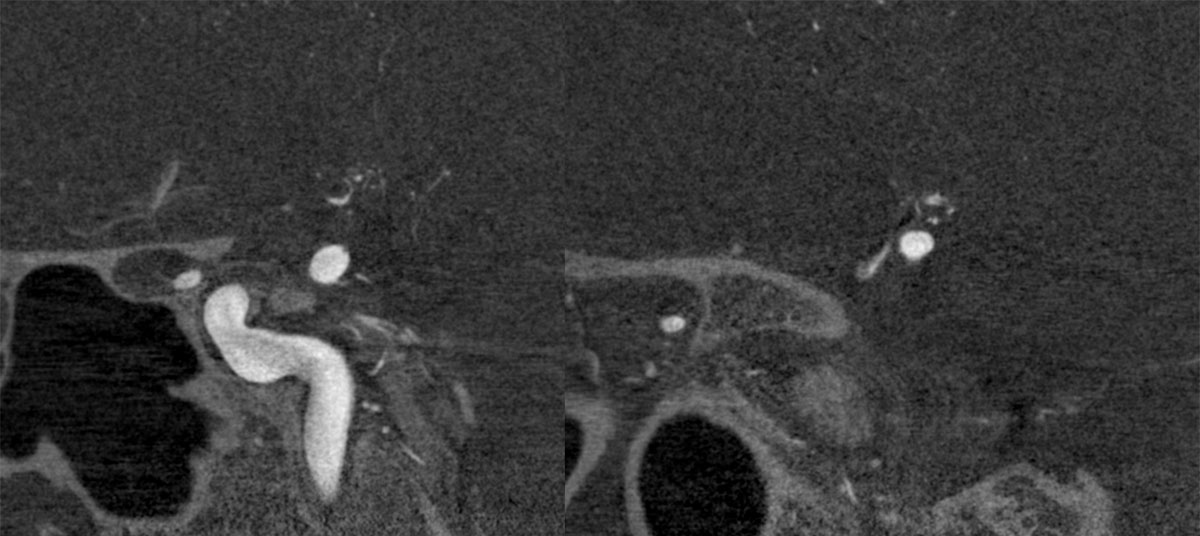

ICA-M1 intracranial dissection EVT

This clinical case presents a 28-year-old female patient presenting with a wake-up stroke, managed with endovascular treatment.

CT – CTA - CTP